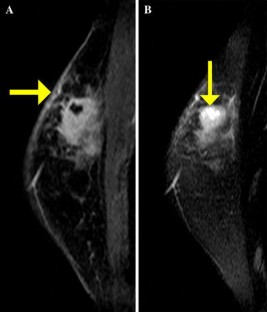

Fig. 2